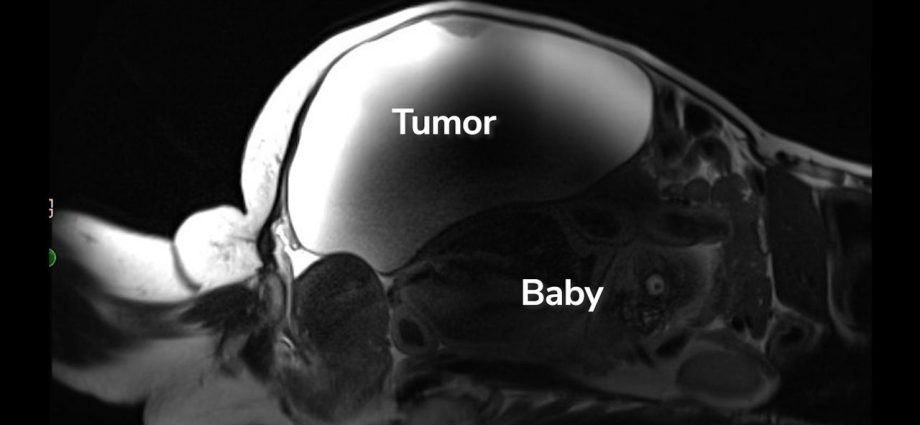

‘Unprecedented’: Woman delivers full-term abdominal pregnancy while also having 22-pound cyst removed

A California woman was scheduled to have a large cyst removed but, in the lead-up to the procedure, learned she had a rare ectopic pregnancy…Continue Reading